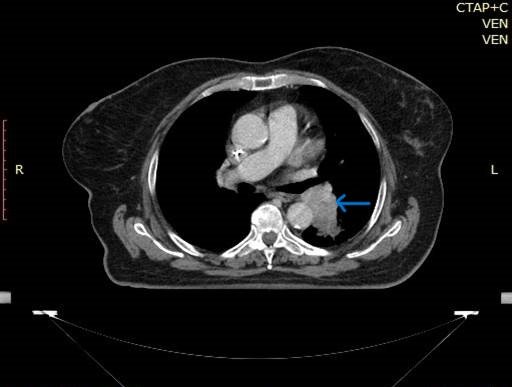

CT (computer tomográf) felvétel tüdőrákról

Fotó: Amethyst sugárterápiás központ